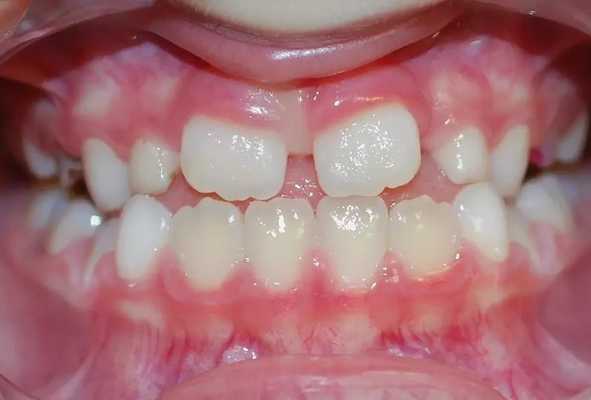

В этот переходный период, когда зубной ряд состоит из молочных и постоянных зубов, у ребенка сменный прикус.

Ранний сменный прикус.

Во время сменного прикуса идет активный рост челюстей и начинает формироваться постоянный прикус. Поэтому важно следить за тем, в какой последовательности у ребенка зубы сменяют друг друга

Особенности сменного прикуса

Итак, с прорезыванием первого постоянного моляра начинается сменный прикус. Сменный прикус представляет собой более высокую степень развития и дифференцировки жевательного аппарата. Он характеризуется наличием временных и постоянных зубов, который продолжается от 6 до 12—14 лет.